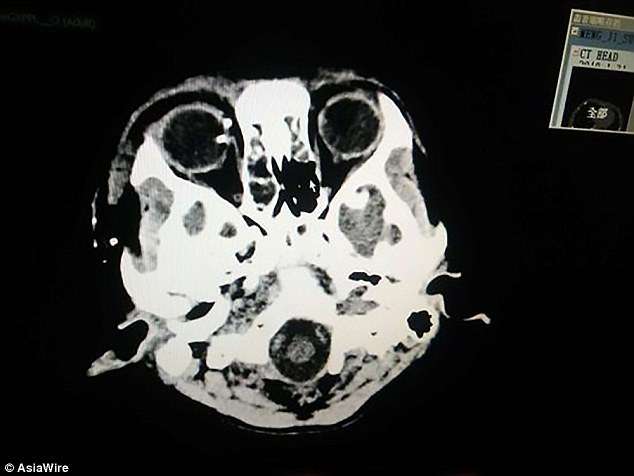

▼小明的右手食指被炸飛,其他手指受傷,眼睛也被炸傷了。他又痛又怕,直接暈了過去。家人連忙帶他去醫院治療,經過檢查,小明的眼球有異物、肺部挫傷、右手臂和手指有粉碎傷。醫生立刻為他做前臂皮瓣轉移修復術、拇指、中指、環指再植手術。

手術非常順利,現在小明的手掌已經恢復供血,有98%的機率痊癒。接下來他還要治療眼睛。手機爆炸太可怕了,希望小明堅強起來,快點恢復健康吧~